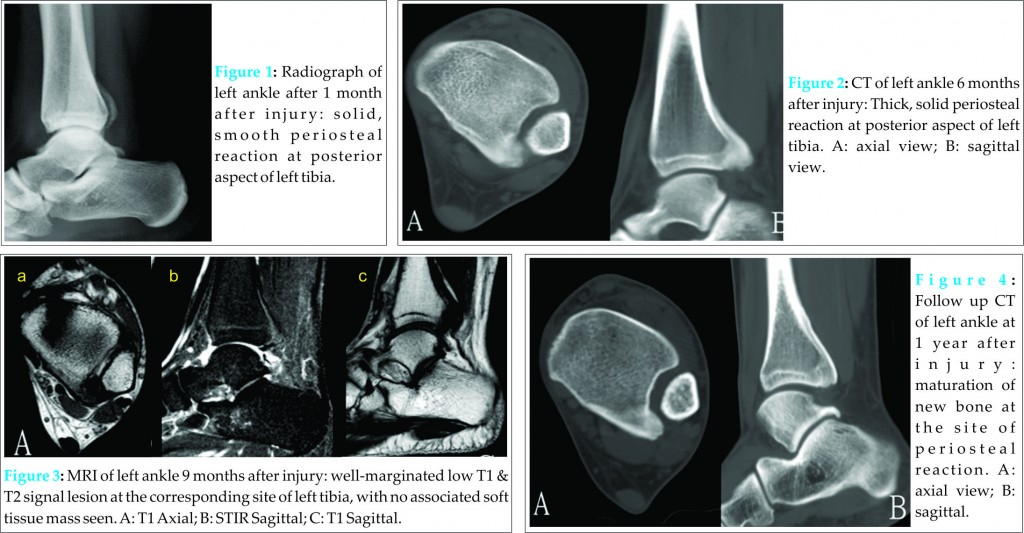

A 25 year old gentleman had an inversion injury to his left ankle. He complained of lateral ankle and posterior heel pain and swelling after the injury. He was treated by a bonesetter and the lateral ankle pain subsided but he still complained of posterior heel pain. He attended our orthopaedic clinic 5 months after the injury. The posterior heel pain had improved by that time. Radiograph of his left ankle revealed solid, smooth periosteal reaction at posterior aspect of left distal tibia (Fig. 1). No definite fracture was detected. MRI showed periosteal reaction at the corresponding site, which was better demonstrated in CT scan (Fig. 2). Follow up MRI at 9 months after the injury (Fig. 3) and CT at 1 year after the injury (Fig. 4) showed maturation of the new bone formation at the site of periosteal reaction. Findings are compatible with subperiosteal hematoma formation from injury, which ossified with time. The patient became asymptomatic 9 months after the injury and there was no more local tenderness or swelling.